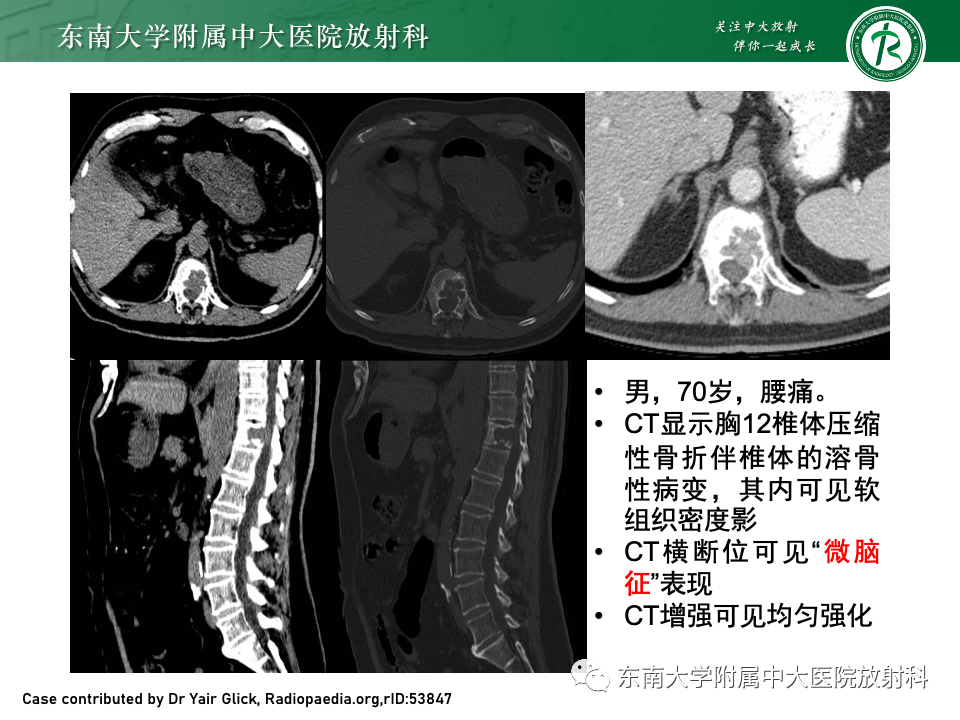

男,51岁

主诉:腰背部疼痛伴行走困难进行性加重10月

辅助检查:免疫球蛋白定量分析正常,尿轻链KAPPA LAMBDA定量:尿KAP:12.9mg/L↑。M蛋白分析:检出κ型IgG单克隆免疫球蛋白抗体